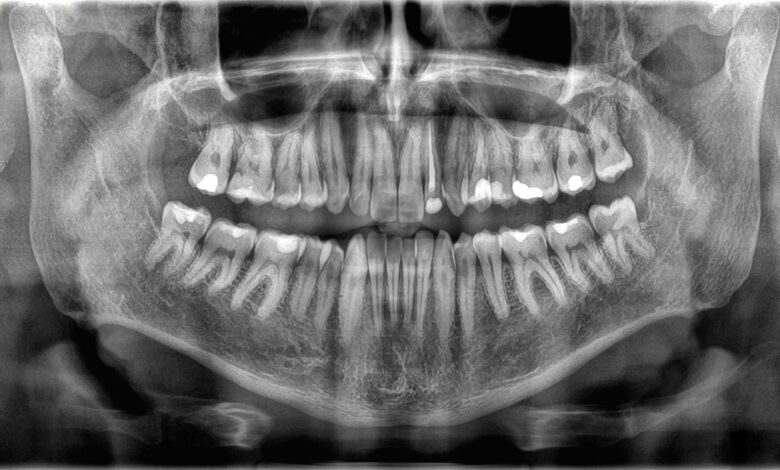

Пошто кости и зуби обављају различите послове, они су такође различито грађени. Спољашња структура зуба се назива емајлтанак слој минерализованог ткива. Емајл је најчвршћа супстанца у телу – особину коју добијају од кристала упакованих у џем направљен од једињења калцијума и фосфата.

Испод глеђи се налази дентин, врста минерализованог ткива које је нешто мекше од глеђи, али и даље тврдо. Дентин чини већину структуре зуба и садржи мале цевчице које држе крвне судове и нервне завршетке. Језгро зуба је направљено од желеасте супстанце која се зове пулпа, у којој се налази више крвних судова који обезбеђују хранљиве материје зубу и нервима који контролишу осећај у зубу.